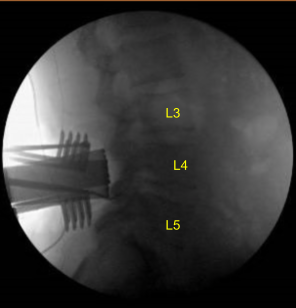

Skin was opened with #10 blade scalpel. Hemostasis was obtained with bipolar. Bovie monopolar and Cobb elevators were used to carry the incision down, incising the fascia and performing subperiosteal dissection exposing the L4, L5 and S1. Self-retaining retractors were placed. A Woodson elevator was placed under the L4 lamina. C-arm unit, which was draped sterilely, was brought into the field and used to confirm the level.

L4, L5 and S1 spinous processes were resected with Horsley rib cutters and Leksell rongeurs. Bone bleeding was controlled with bone wax. Electric high-speed drill with sterile irrigation was used to perform L4, L5 and S1 laminectomy. This was continued with Kerrison rongeurs, carefully protecting the dura. No cerebrospinal fluid or durotomy was identified.

Hypertrophied ligamentum flavum was resected at L4 and L5. Significant epidural lipomatosis similar to preoperative imaging was identified at L5-S1. Lateral recess at L4, L5 and S1 was decompressed with Kerrison rongeurs. Decompression was confirmed with nerve hooks and Woodson elevators. Bilateral L4, L5 and S1 nerve roots were completely neurolyzed with Metzenbaum-Penfield technique and confirmed with nerve hooks.